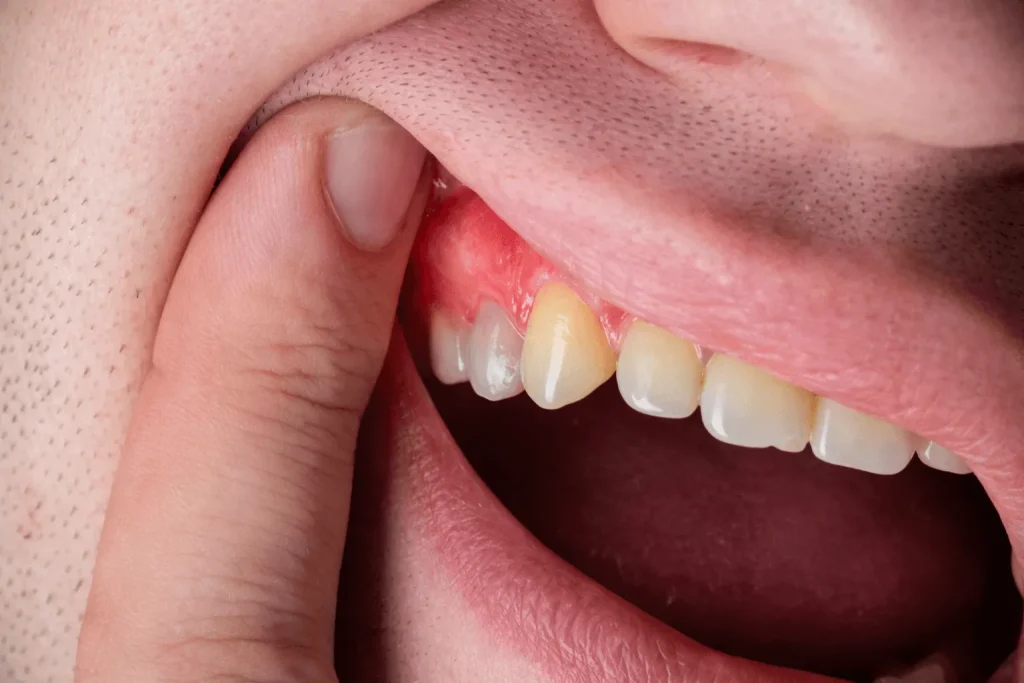

- تغییر رنگ صورتی لثه به قرمز و احساس فشار: از دیگر علائم طبیعی التهاب لثه بعد از کاشت ایمپلنت، تغییر رنگ آن به قرمز و احساس فشار در آن ناحیه است.

۲. علائم هشداردهنده

بر خلاف موارد طبیعی التهاب بعد از ایمپلنت که به آنها اشاره شد، بر اساس مطالعات، مشاهده بعضی از علائم میتواند نشان از احتمال عفونت در پروسه درمان باشد؛ بنابراین بهتر است در صورت مواجه با این علائم، هر چه سریعتر به پزشک مراجعه کنید.

- سنگینی تورم در یک طرف: زمانی که تورم بعد از ایمپلنتگذاری، شدید میشود و احساس سنگینی در یک طرف ایجاد میکند، به پزشک مراجعه کنید.

- تداوم خونریزی و ترشح چرک: کمی خونریزی در روزهای اول کاشت ایمپلنت، اتفاقی عادی است. اما درصورتیکه خونریزی ادامهدار بود و چرک از ناحیه ایمپلنت ترشح کرد، میتواند نشانه عفونت باشد.

- درد کوبشی برای بیشتر از ۷ روز: وجود درد ضرباندار که بیش از هفت روز ادامه دارد، میتواند به معنای وجود عفونت ایمپلنت باشد.

- حس طعم فلز یا بوی بد دهان: دو نشانه دیگر که ممکن است به معنای وجود مشکل در کاشت ایمپلنت و عفونت کردن آن باشد، احساس طعم فلز و بوی بد غیرمعمول در دهان است.

- لقی روکش یا حرکت اباتمنت: لق شدن روکش ایمپلنت یا شل شدن اباتمنت میتواند میان ایمپلنت و لثه فاصله ایجاد کند و فضای رشد باکتریها را در این فاصله فراهم کند.

- احساس حرارت در محل ایمپلنت و تب: احساس گرما و تب در محل ایمپلنت، میتواند نشانه عفونت باشد.